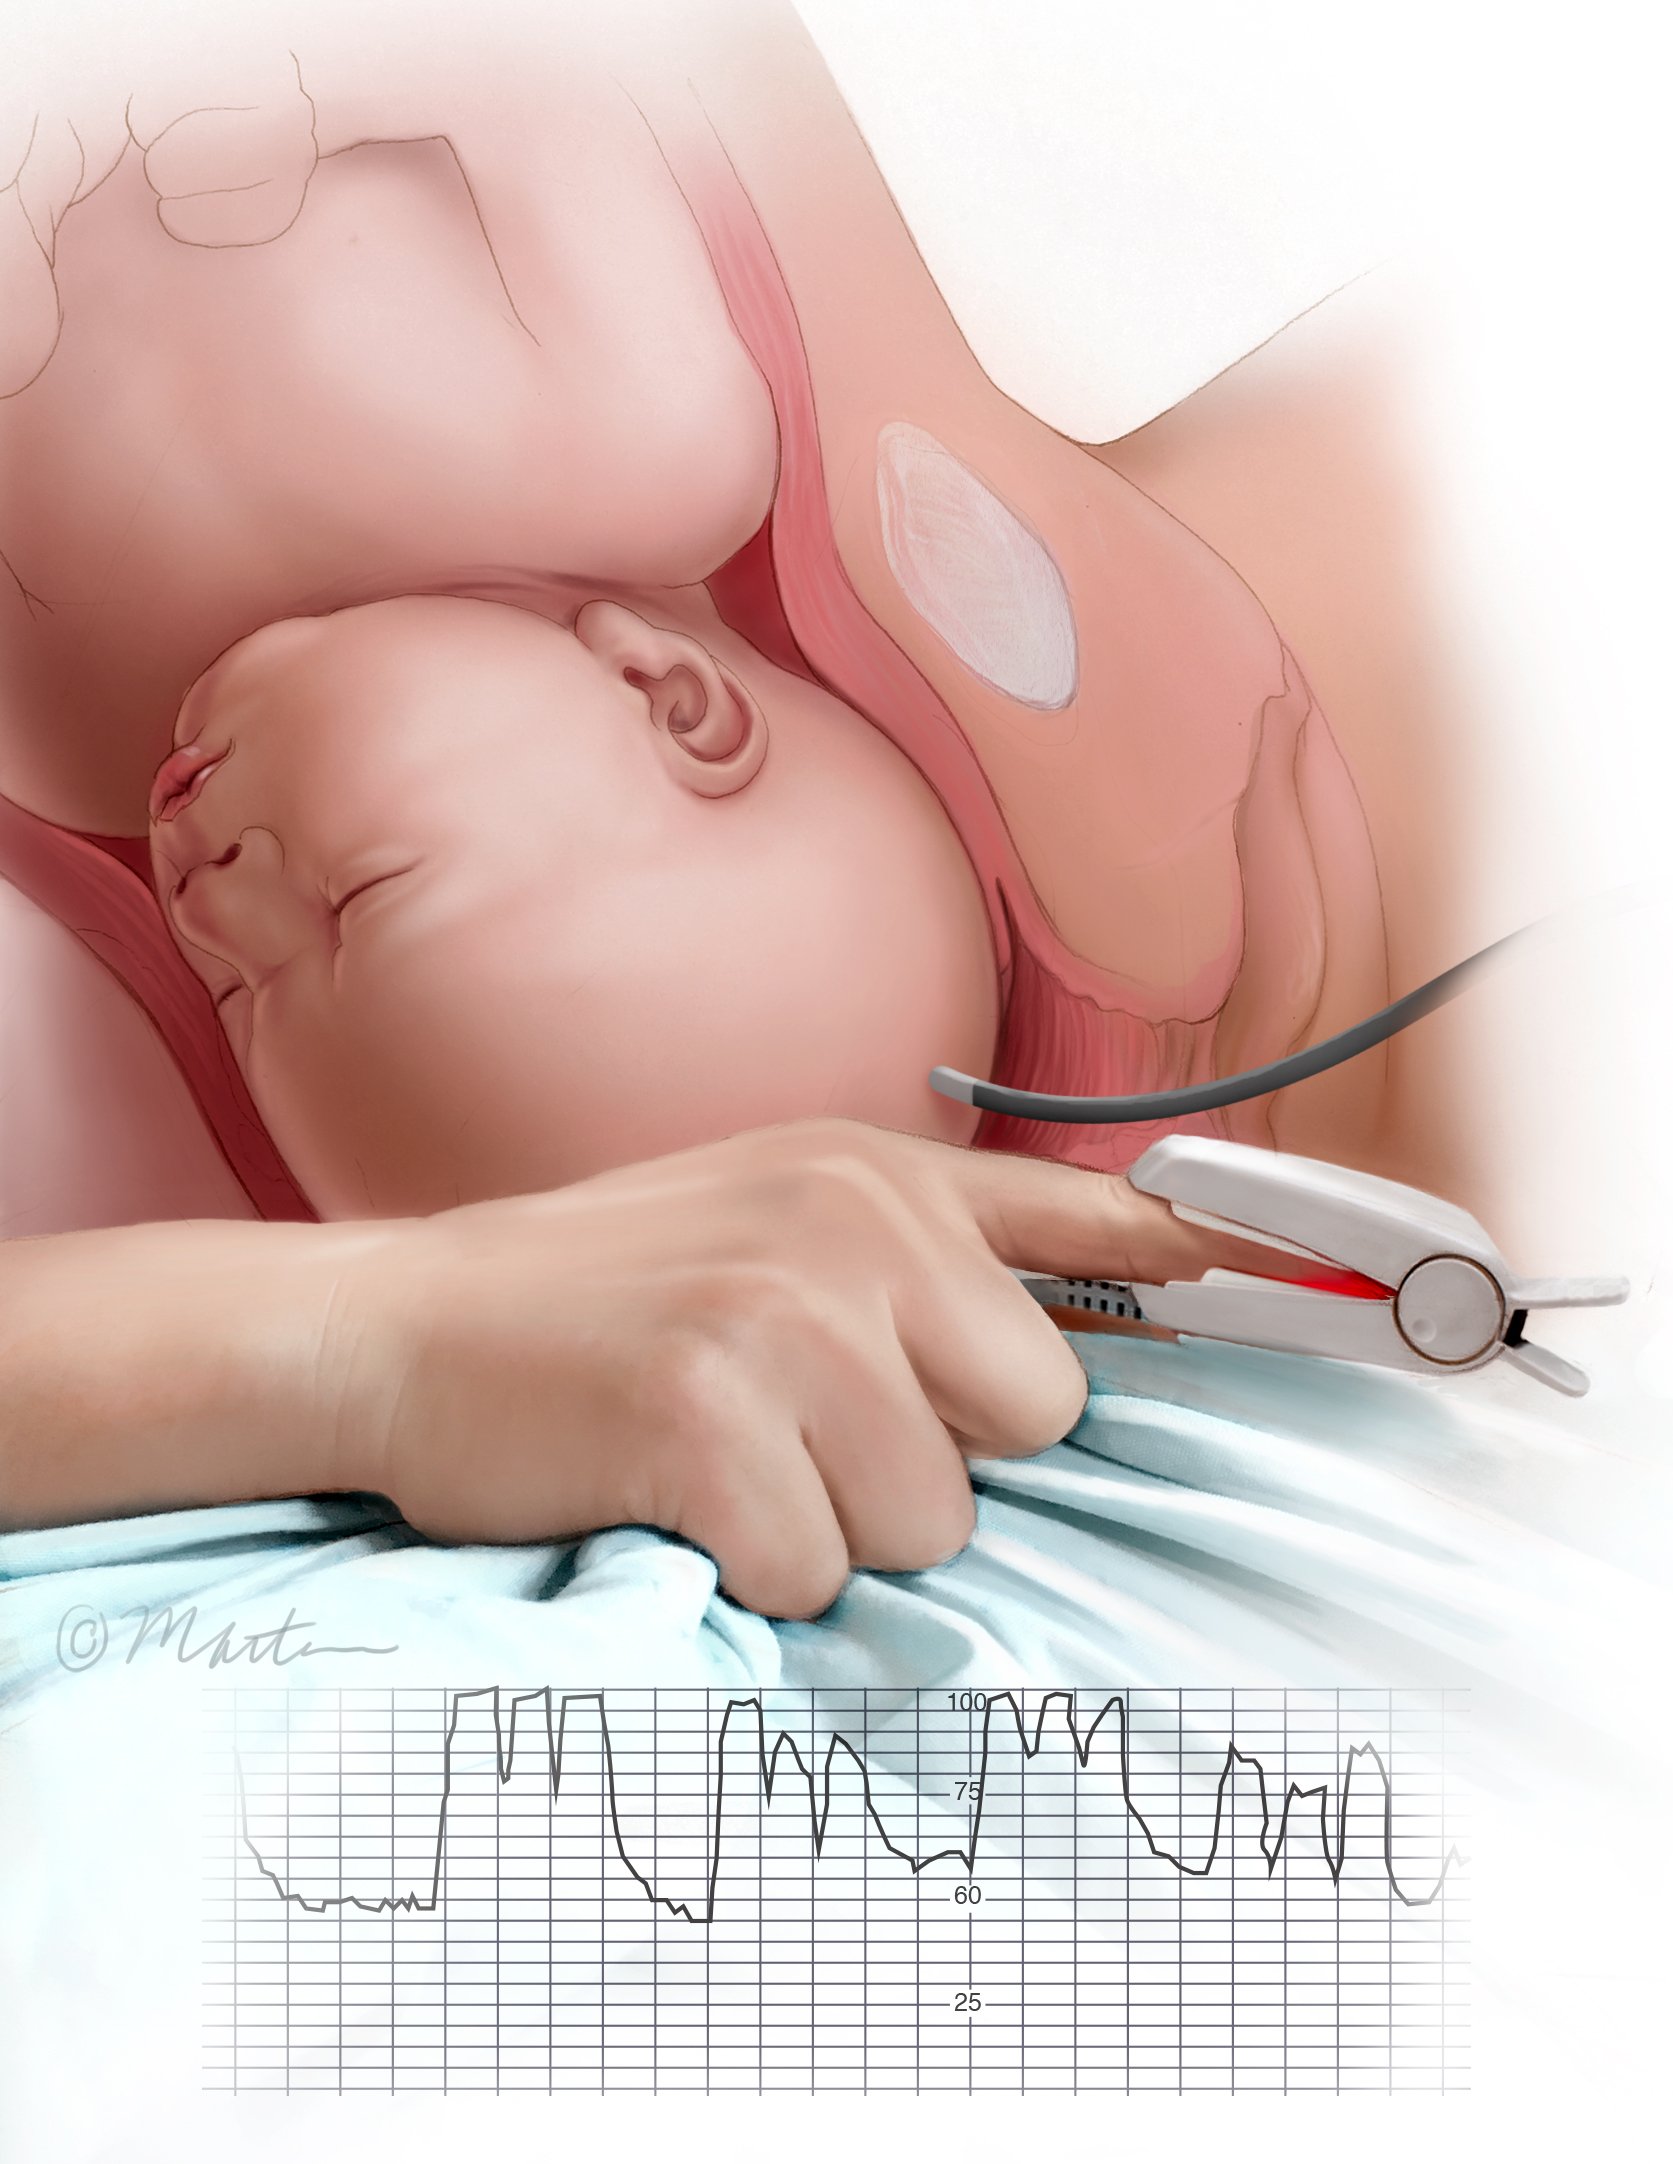

Fetal Heart Rate